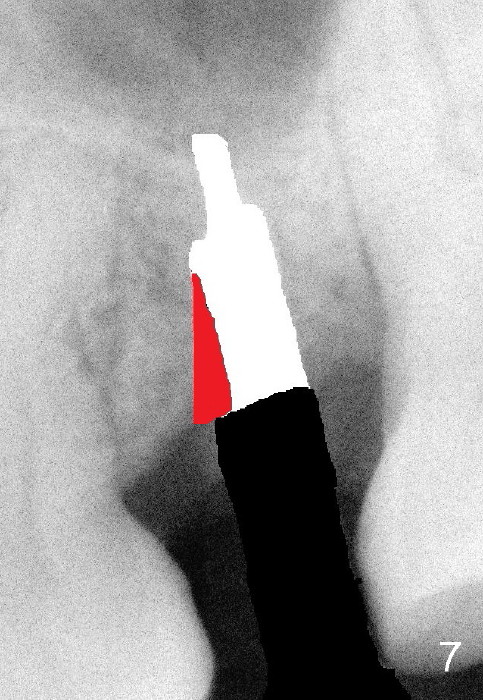

How to fix it? As soon as the deviation is noted, remove the drill/reamer/implant (Fig.6). Remove the resistant area with a Lindamann bur (Fig.7 red region). The implant should be able to be placed in a correct position (Fig.8).